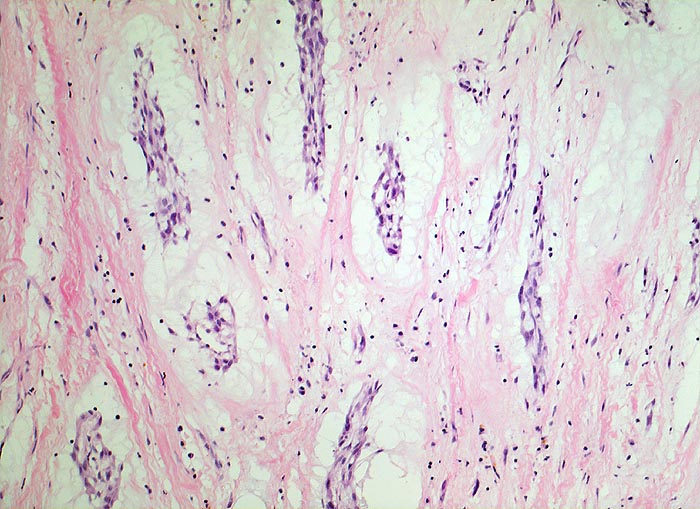

AP/ Vorhofmyxom

Vorhofmyxom

Herz Vorhof